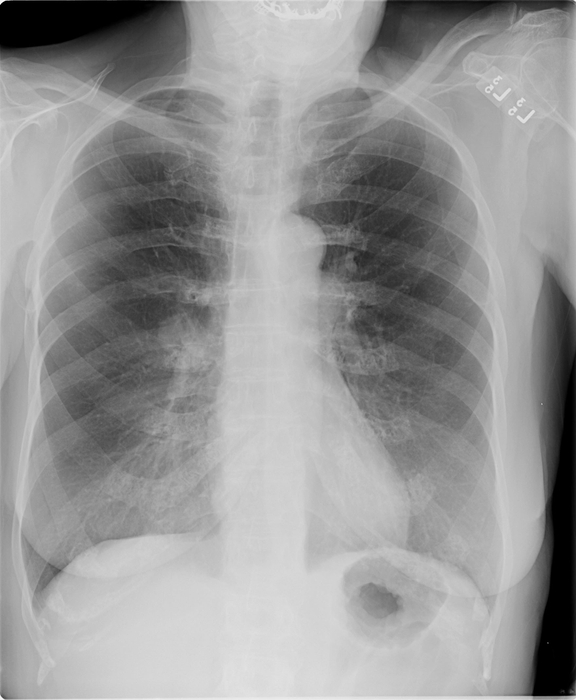

胸部読影支援システム「ClearReadシリーズ」は、先端画像処理技術により胸部X線画像や胸部CT画像の肺野部の視認性を高めることにより、医師が多数の画像を観察してわずかな変化を発見しそれが病気かどうかを判断する読影業務を支援します。あらゆる装置で撮影した画像に対し処理が可能であり、院内の運用を変更することなく、読影補助画像を医師が参照できるようになります。当社が国内で販売開始して以来、「ClearReadシリーズ」は健診施設に限らず一般診療を行う病院でも使用され、導入した施設からは、「読影精度や読影速度が向上した」、「心的ストレスが低減された」などの声が寄せられています。

胸部X線画像の肋骨や鎖骨などの骨組織を透過した画像を生成し、骨組織と重なり検出が困難であった肺結節や異常陰影などの視認性を向上させる。

胸部CT画像の肺血管を透過した画像を生成し、肺結節や異常陰影の視認性を向上させる。